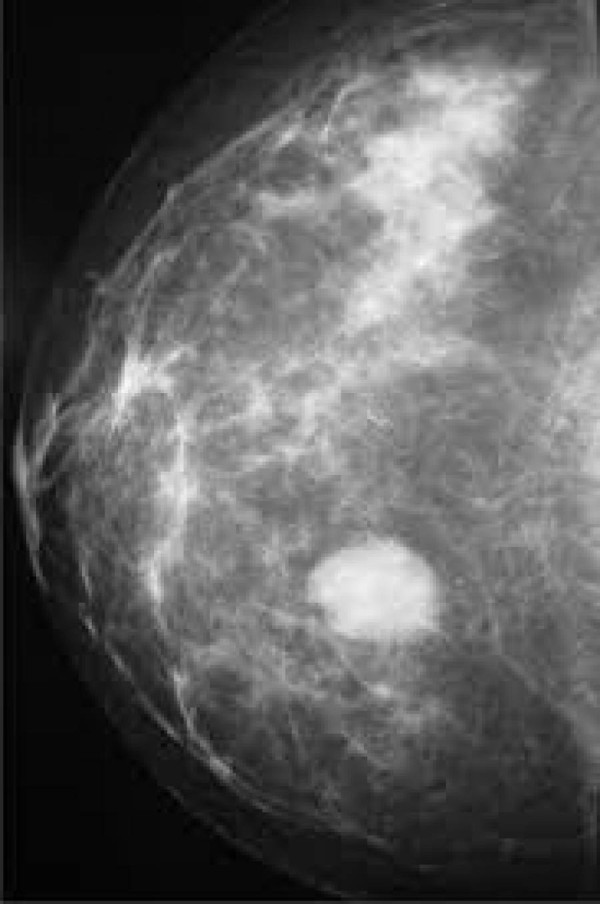

A través de informaciones de trabajadores, que nos piden respetar el anonimato por miedo a represalias, hemos podido constatar que, desde hace meses, diferentes hospitales públicos madrileños mantienen infrautilizados sus mamógrafos en varias franjas horarias.